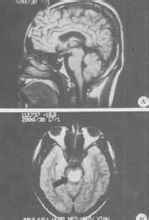

腦幹腦炎患者,女,35歲,湖南衡陽市郊農民。因行走無力,視物模糊5天,加重伴言語不清,嗜睡2天,於2005年11月24日急診入院。2005年11月20日上午,患者在廣州某鎮探親時家務勞動後,上樓時出現行走無力,下午自覺視物模糊,不伴發熱、惡寒、頭痛、頭暈、咳嗽、咽痛、噁心、嘔吐等症狀。11月21日上午患者步行到廣州市某鎮醫院按"上呼吸道感染"治療無效。11月22日下午患者出現行走無力加重,需人攙扶,並出現言語欠清晰、精神差,被家人於當晚送回湖南當地縣人民醫院診治。查體:嗜睡,反應遲鈍,言語欠清晰,口角向左歪,伸舌右偏,右上下肢肌力IV級,左上下肢肌力正常,病理反射(-)。頭顱CT平掃未見異常。按"腦梗塞"治療病情無好轉,故於11月24日下午轉至我院神經內科重症監護病房按重症腦梗塞診治。入院時查體:T36.7℃P86次/分R20次/分BP105/71mmHg嗜睡,言語欠清晰,右眼瞼稍下垂,右眼內收及左眼外展受限,右側鼻唇溝稍變淺,伸舌右偏,雙側咽反射減弱,心、肺、腹均未見異常,左上、下肢肌力IV級加,右上、下肢肌力III級加,四肢肌張力稍低,腱反射減退,指鼻及輪替試驗及感覺功能檢查無法配合。頸軟,克、布氏征(-),右巴氏征(+),左巴氏征(-)。實驗室檢查:血常規:WBC總數:10.4×109/L,分類正常;電解質、肝、腎功能、血脂、血糖及血氣分析均正常。11月25日上午患者出現昏睡,完全性失語,四肢肌力明顯減退,右上肢肌力0級,左上、下肢及右下肢肌力均II級。查頭顱MRI示:中腦與橋腦交界處見片狀稍長T1稍長T2信號,邊界欠清晰,中腦導水管及第四腦室未見明顯受壓;頭顱MRI增強:腦幹異常信號,未見明顯強化,考慮腦幹梗塞。11月26日患者陷入淺昏迷,腰穿查腦脊液壓力95mmH2O,外觀無色,清亮,潘氏實驗(+),總蛋白定量0.58g/L,白細胞數76×106/L,單個核細胞90%,多個核細胞10%,葡萄糖2.59mmol/L,氯化物117mmol/L,故診斷為腦幹腦炎,給予地塞米松10mg靜滴,每日一次,同時予抗病毒,抗感染等治療,12月2日患者意識轉清醒,但言語模糊不清,右上肢肌力II級,右下肢肌力0級,左上下肢肌力II-III級。14天后停地塞米松改為口服強的松30mg/天,逐漸減量,患者入院第20天因經濟困難出院,出院時查體:右眼內收及左眼外展受限,伸舌稍右偏,雙上肢肌力III-IV,雙下肢肌力III級,病理征陰性,複查腦脊液:壓力180mmH2O,無色,清亮,潘氏實驗(-),腦脊液蛋白定量0.23g/L,白細胞數16個106/L,單核細胞為主,葡萄糖3.4mmol/L,氯化物128mmol/L。2006年1月17日複診:患者仍行走不穩,需人攙扶。查:神清語利,計憶力、定向力、記算力正常,雙眼球運動正常,雙鼻唇溝對稱,伸舌稍右偏,四肢肌力肌張力正常,雙巴氏征陽性,深淺感覺檢查正常。雙側指鼻試驗稍差,Romberg征睜眼(+),閉眼(+)。腦電圖正常;視覺、腦幹聽覺誘發電位檢查:右眼VEP潛伏期延長,波幅在正常範圍內;左眼VEP潛伏期、波幅在正常範圍內;右耳BAEP波形分化不良,左耳BAEPⅠ、Ⅲ、Ⅴ波幅,潛伏期正常;四肢肌電圖檢查:左腓總神經運動傳導波幅降低。2006年3月15日隨訪,患者行走正常,完全康復。查體無異常。